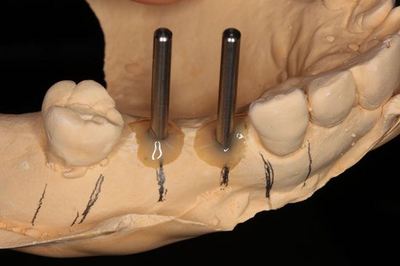

![]()

いつものように埋入計画を立て、サージカルステントの作製をします。